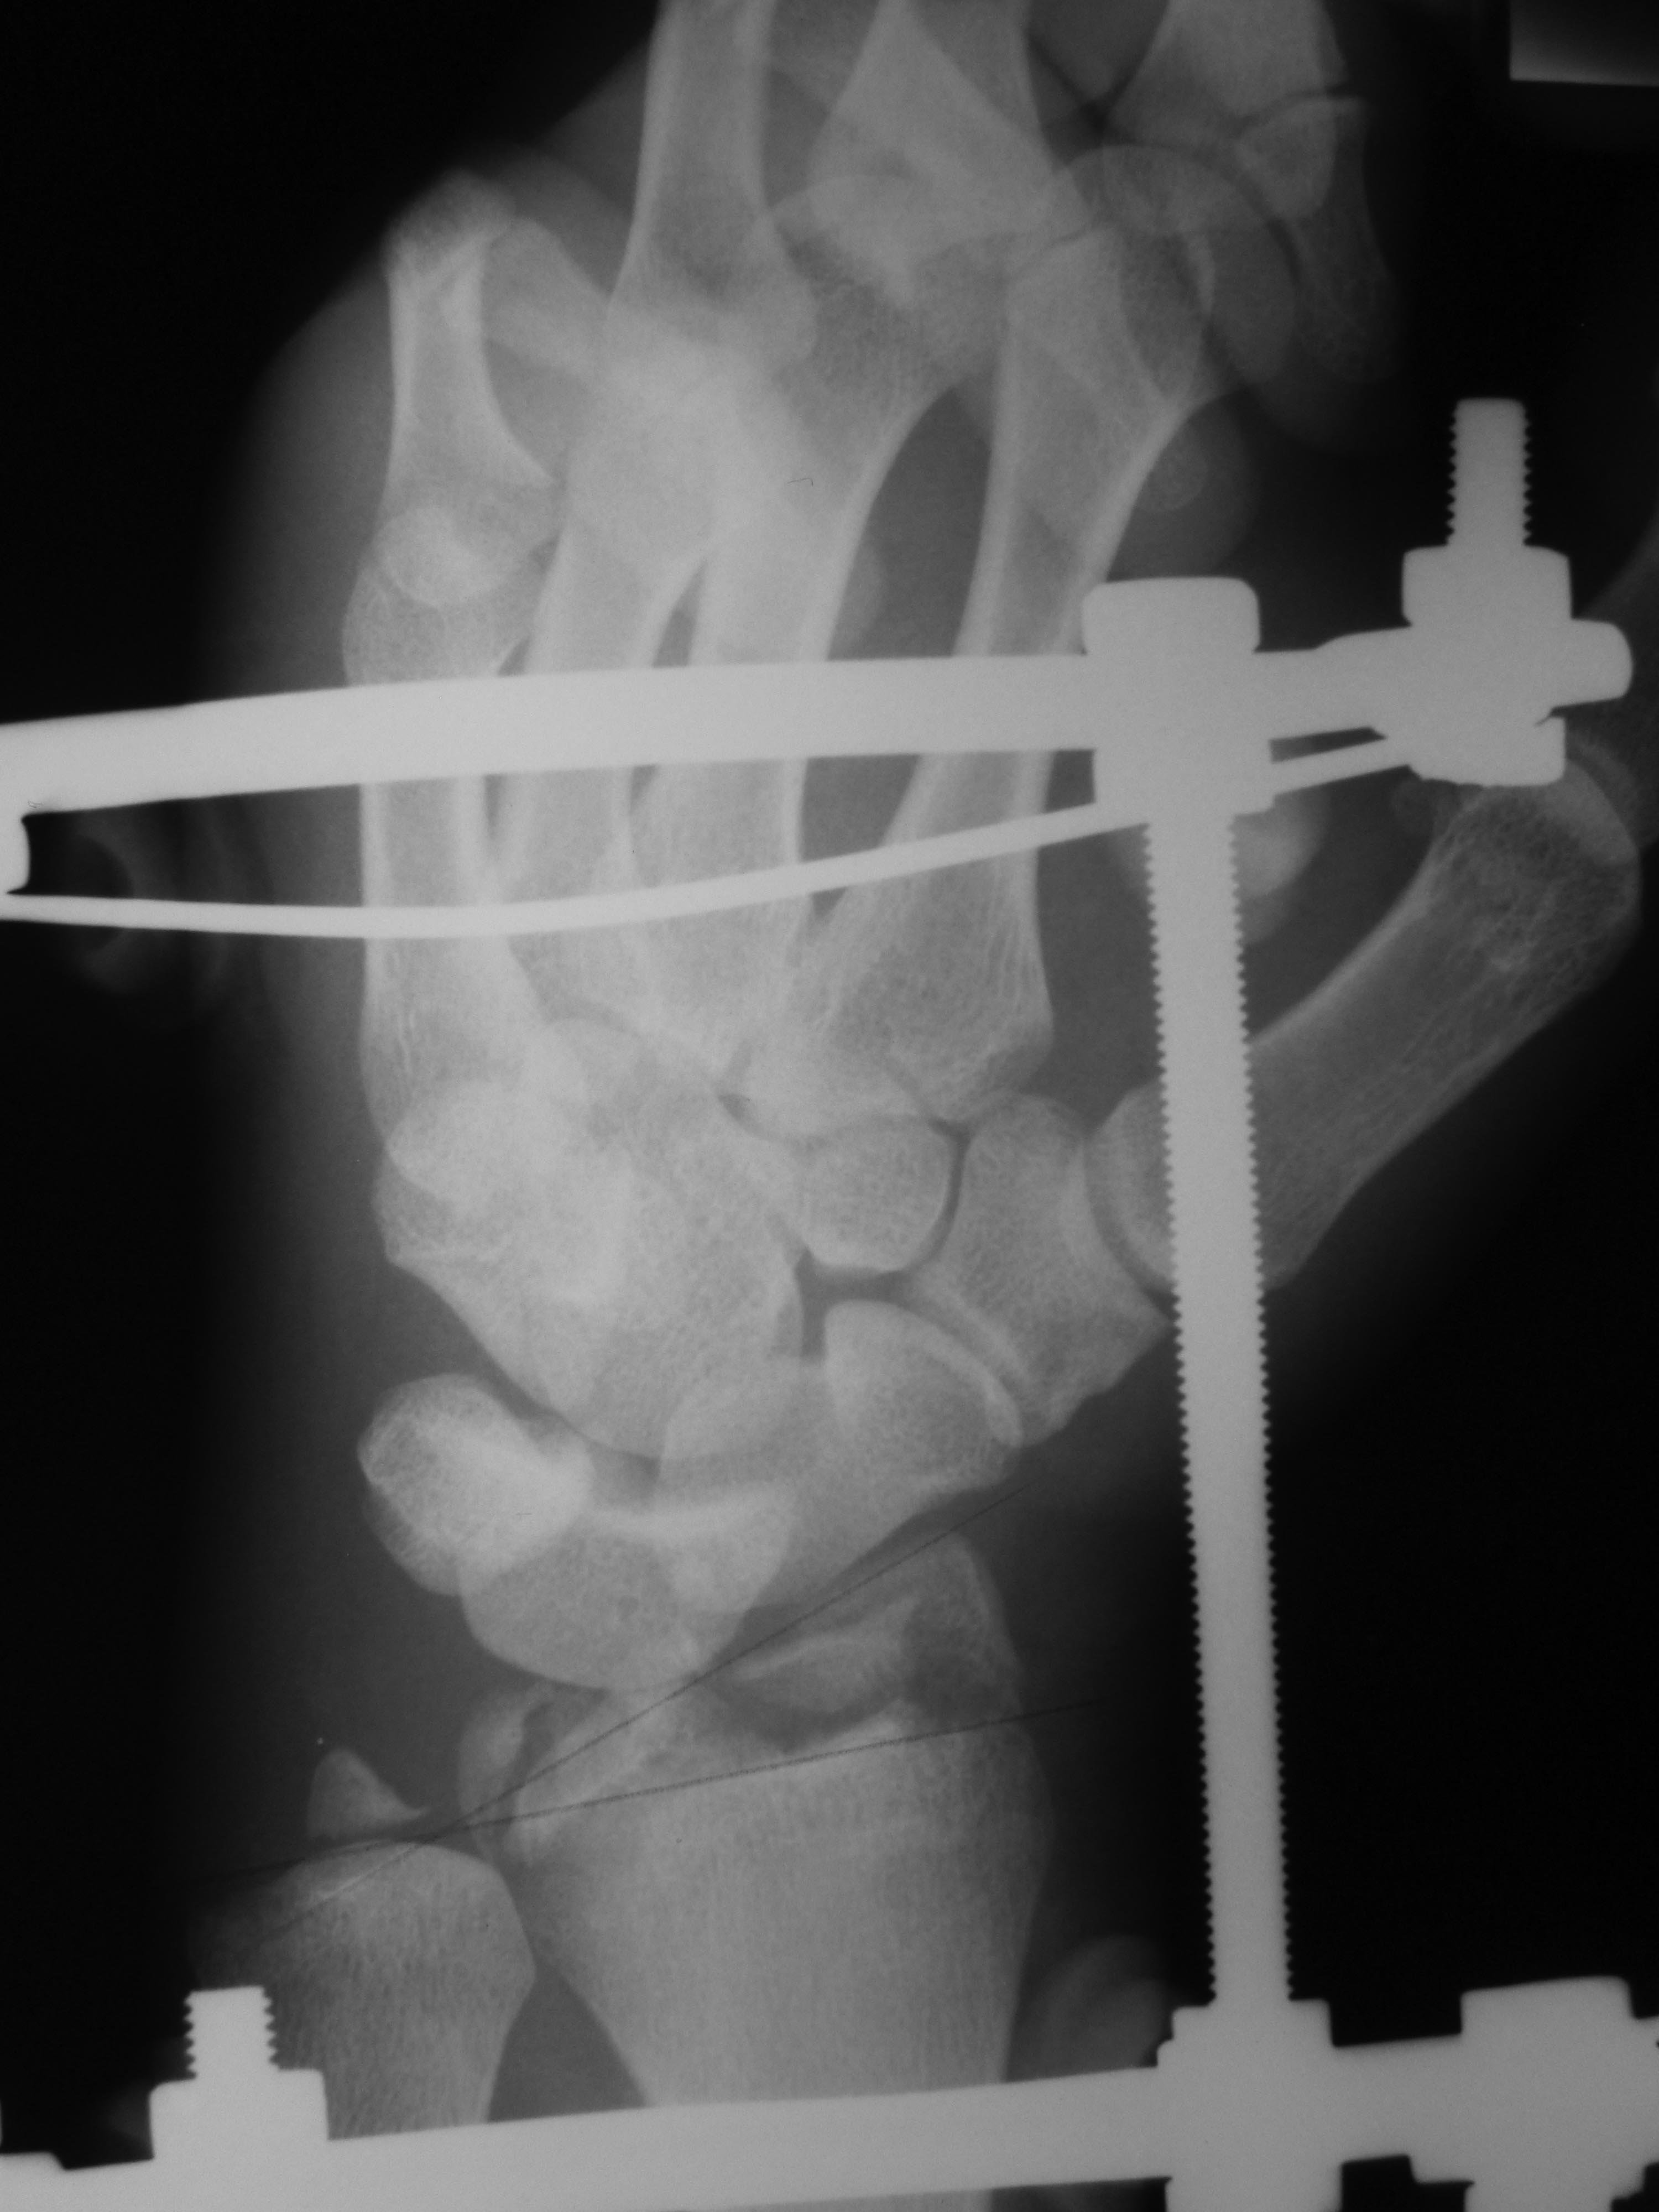

Рентгенограммы:

Здравствуйте! Кисть в подвывихе к тылу. Возможно стоит вставить в дистальное кольцо шарниры или вставки, для того, чтобы тракцию осуществлять под углом, т.е. в ладонную сторону. Пример аппарата во вложении, только тут тракция в другую сторону - к тылу, а вам надо в ладонную.

Приветствую! Учитывая многооскольчатый характер перелома (тип С) и открытый характер перелома конечно АВФ, только нужны шарниры на дистальное кольцо и локтевая девиация

Это классический переломо-вывих в лучезапястном суставе, выделенный АО в отдельную подгруппы - 23-В2.3. В свежем случае здесь показано закрытое вправление и наружная фиксация повязками или аппаратом, в качестве окончательного метода для предотвращения нестабильности сустава рекомендуется восстановление капсулы сустава, в первую очередь тыльной - т.е. репозиция и фиксация всех этих мелких фрагментов, послеоперационная иммобилизация аппаратом внешней фиксации